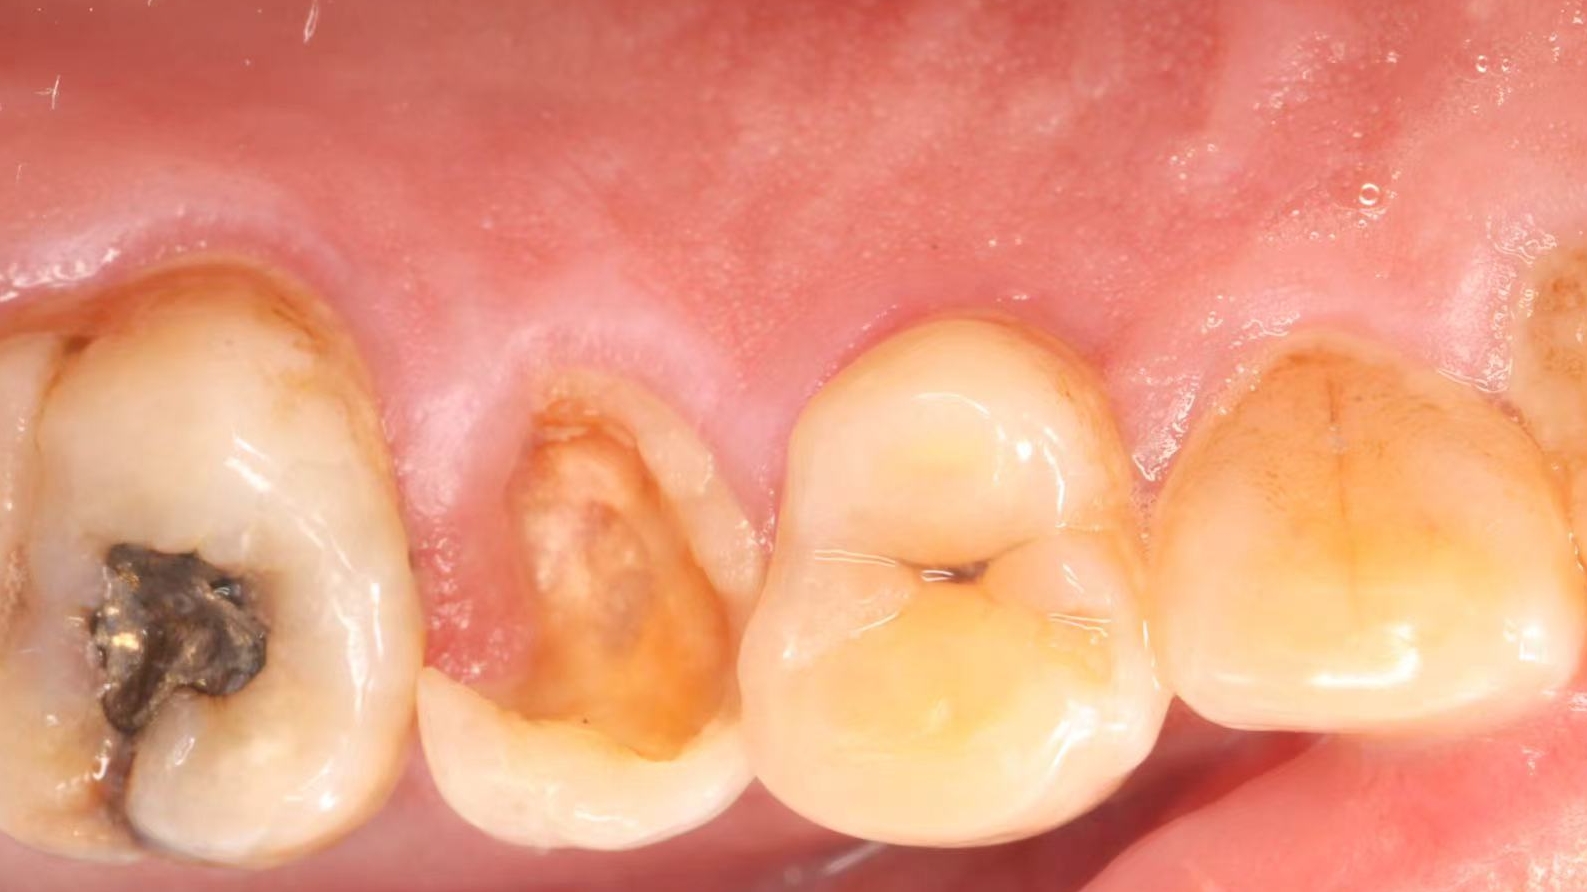

June 20, 2025: The patient's chief complaint is that endodontic treatment was performed on the right maxillary posterior tooth abroad, and a deep carious lesion has been recently detected, requiring restoration. The following are the intraoral photographs taken upon the patient's first visit: a large carious lesion is visible on the occlusal surface of tooth 15 (FDI numbering), with only the buccal wall remaining. Percussion test and cold-hot stimulation test showed no response, and yellow obturation material is visible at the root canal orifices.

Treatment Plan: Given the patient’s refusal of extraction and implant placement, conservative treatment is adopted: retreatment of the root canal followed by post-and-core restoration.